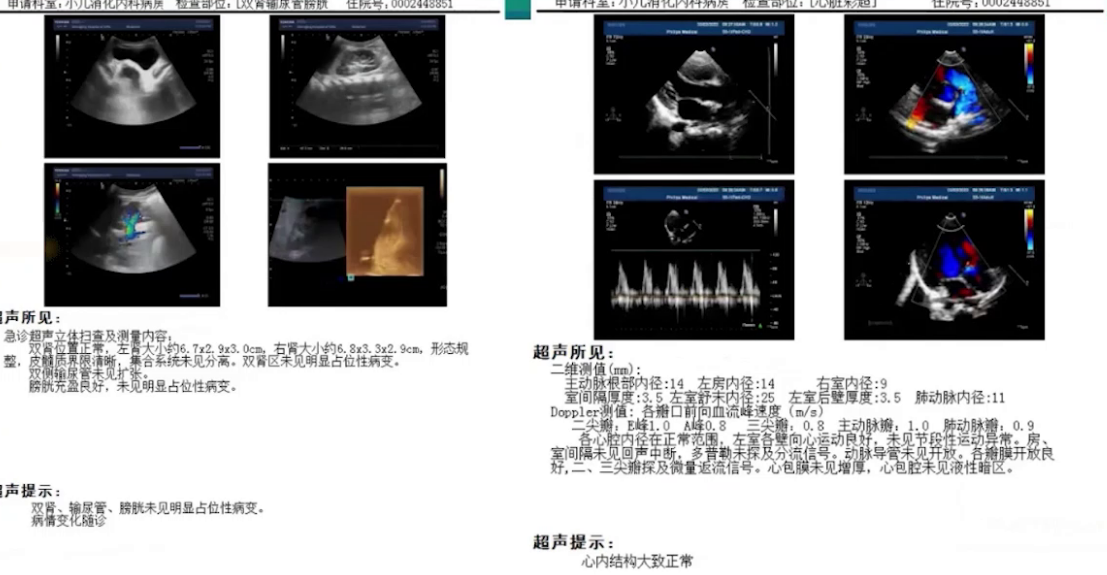

外院:腹腔超声提示少量腹腔积液(1.3cm),肝胆脾胰彩超显示胆囊壁水肿增厚、胰腺肿大伴腹腔积液及左侧胸腔积液(0.8cm)。

本院:全腹增强CT排除腹腔肿瘤及巨大胃黏膜肥厚症,心脏彩超和肾脏彩超未见异常。